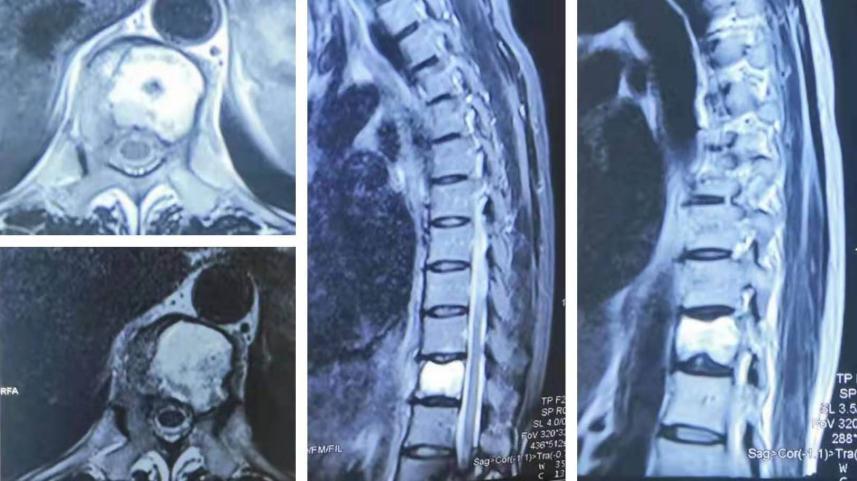

术前MRI检查

谭磊副院长仔细阅读患者所有影像学资料后,认为患者胸11椎体侵袭性血管瘤可能性大,胸11椎体被肿瘤破坏近2/3,如果不及时治疗,不恰当的活动可能导致椎体骨折,造成严重脊髓功能障碍而致瘫痪。当机立断,经穿刺活检病理回报考虑为血管瘤,ECT检查未发现其他部位有肿瘤的存在。